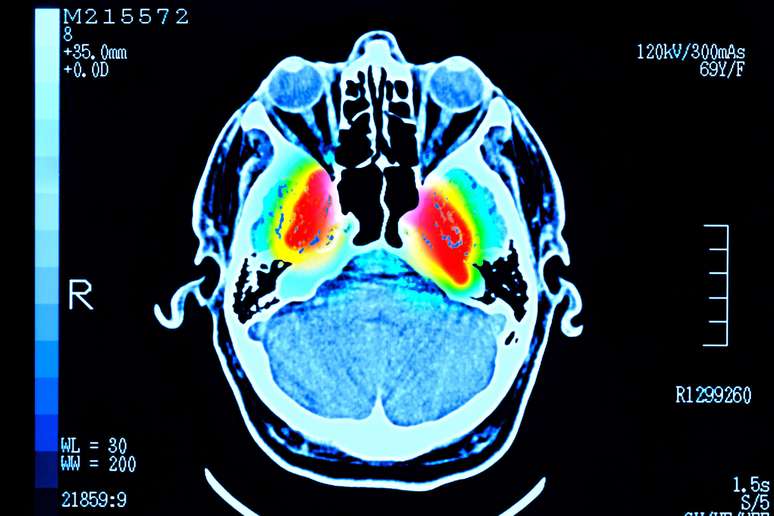

90 வயதிற்குட்பட்ட சுமார் 4,000 பேருக்கு ஸ்கேன் செய்யப்பட்டது, இது அவர்களின் மூளை செல்களுக்கு இடையிலான தொடர்புகளைக் காட்டியது.

நேச்சர் கம்யூனிகேஷன்ஸ் என்ற அறிவியல் இதழில் வெளியிடப்பட்ட ஆய்வில் சேகரிக்கப்பட்ட மூளை ஸ்கேன்களின் அளவு காரணமாக இந்த வடிவங்கள் இப்போது தோன்றுகின்றன.